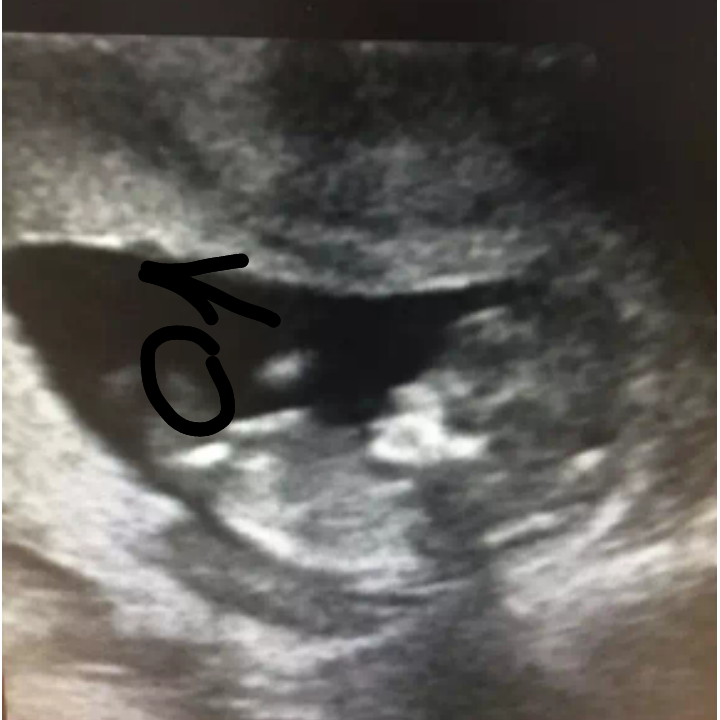

Бугорок

вроде бы девочка

Похоже на девочку

Я бы предположила девочку. Но это из серии погадать, фото ведь "поплыло".

на фото на девочку похоже